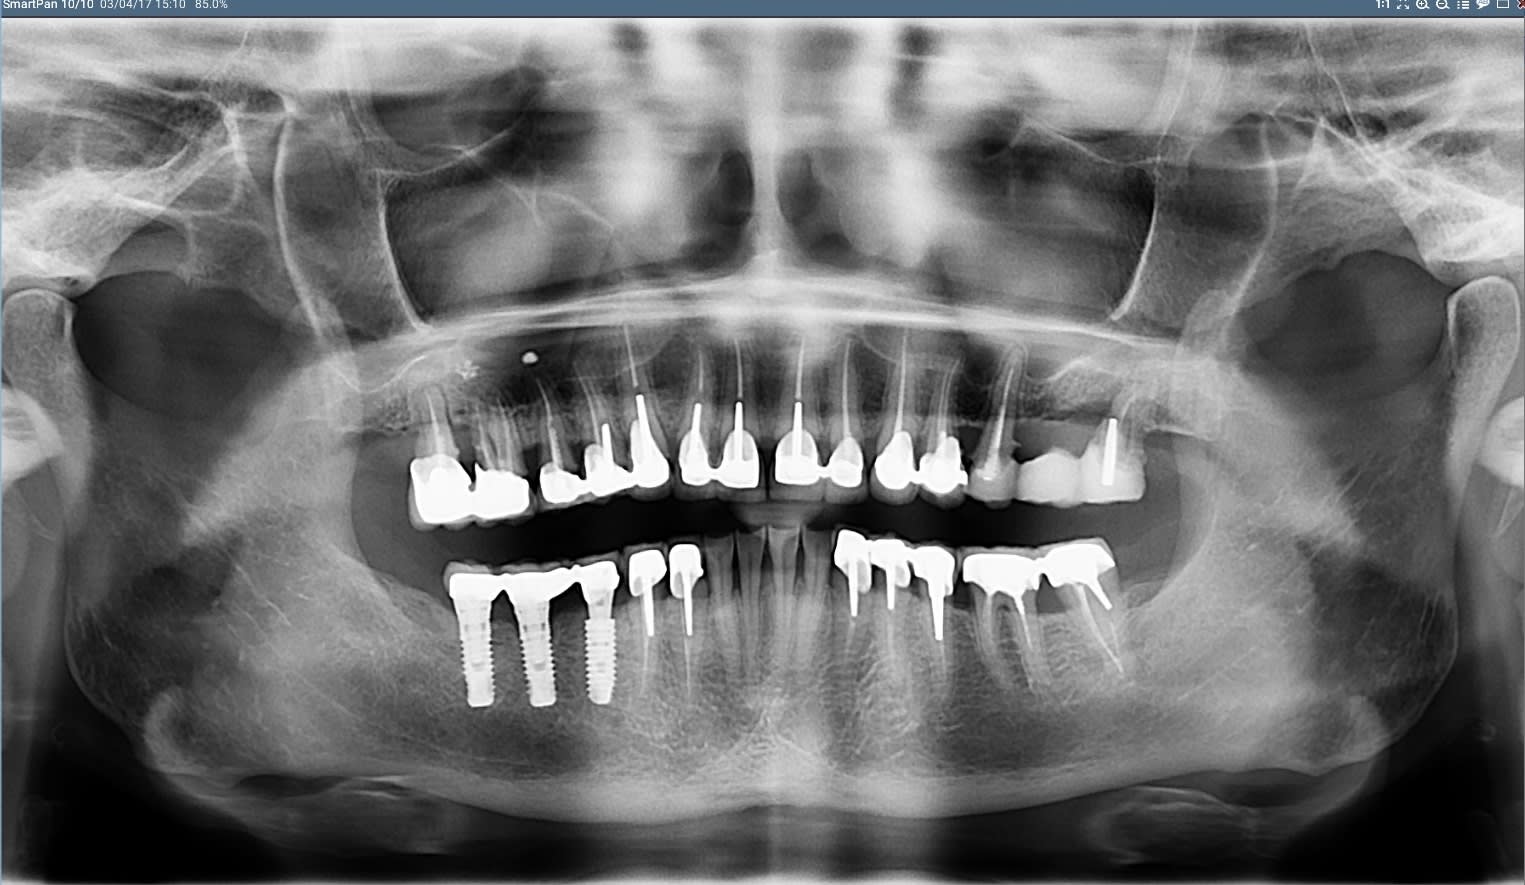

03/04/2017 à 15h46

12 ans et on attaque l'implanto à gauche

Bruxogirl 2 orikum - Eugenol